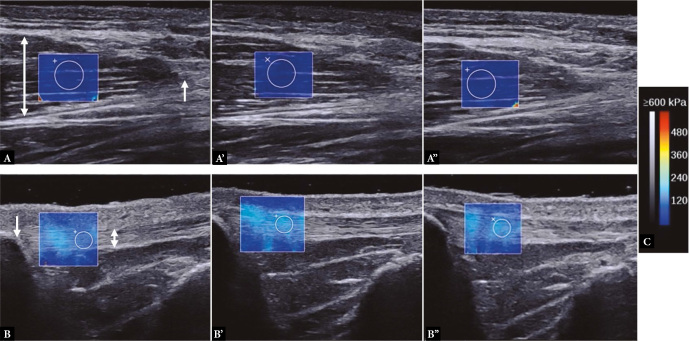

Material and methods: Fifteen healthy men (age: 26.4 ± 2.2 years) were instructed to perform 5 min of voluntary static stretching of their right rectus femoris muscles five times a week for four weeks. The participants adjusted their stretching inrectus femoris muscle tensity to a point immediately before experiencing discomfort or pain. The Young's modulus of the rectus femoris muscle and the knee-flexion range of motion were measured as indicators of flexibility. The Young's modulus was measured using shear wave elastography. Measurements were performed at baseline, as well as at two and four weeks after the stretching program started. A generalized linear mixed model was used to assess the change in the Young's modulus after the stretching program and the effects of the Young's modulus on the knee-flexion range of motion.

Results: The Young's modulus of the rectus femoris muscle decreased after two and four weeks of stretching compared with the baseline (p = 0.0004 and p <0.0001, respectively). The Young's modulus of the rectus femoris muscle and the four-week duration of stretching affected the knee-flexion range of motion (p = 0.0242 and 0.0016, respectively).

Conclusions: Shear wave elastography quantitatively revealed that several weeks of static stretching increased the flexibility of the rectus femoris muscle in healthy men. A four-week static stretching regimen reduced the Young's modulus of the rectus femoris muscle and increased the knee-flexion range of motion.